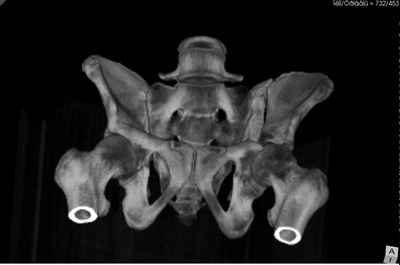

Добрый вечер уважаемые коллеги. Госпитализирован пациент с переломом таза 9-ти месячной давности (лечился где-то в районе консервативно). Помогите определиться с оптимальным вариантом хирургического доступа, фиксации.

Пациенту чуть больше сорока лет, работал в МЧС, после ДТП лечился по месту жительства консервативно. Жалобы пациента на постоянные боли в месте перелома, ощущение подвижности в месте перелома при ходьбе. Передвигается без дополнительной опоры, хромота не щадящая. Клинически отчетливо определяется патологическая подвижность крыла левой подвздошной кости. R-ммы не высылаю, сразу 3-D, если не хватит дошлю снимки.

Андрей, на 3d снимках не видно соотношение суставных поверхностей, величину диастаза в ложном суставе и состояние головки (может уже протез нужен).